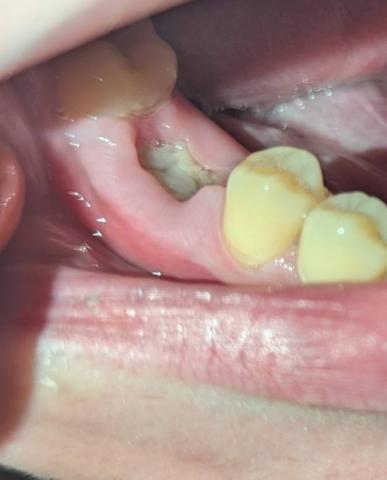

Case Analysis: Suspected Tooth Infection and Gum Inflammation

Observation

The image shows a lower molar area with visible gum irritation, tissue swelling, and darkened debris around one tooth. The surrounding gingiva appears inflamed and possibly infected. There are also signs of decay or necrotic tissue that may indicate an advanced tooth infection or abscess formation.